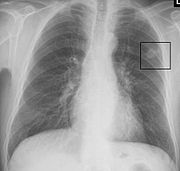

![]() Cross section of a human lung. The white area in the upper lobe is cancer; the black areas indicate that the patient was a smoker. |

Lung cancer may be seen on chest x-ray and computed tomography (CT scan). The diagnosis is confirmed with a biopsy. This is usually performed via bronchoscopy or CT-guided biopsy. Treatment and prognosis depend upon the histological type of cancer, the stage (degree of spread), and the patient's performance status. Possible treatments include surgery, chemotherapy, and radiotherapy. With treatment, the five-year survival rate is 14%.

Performing a chest x-ray is the first step if a patient reports symptoms that may be suggestive of lung cancer. This may reveal an obvious mass, widening of the mediastinum (suggestive of spread to lymph nodes there), atelectasis (collapse), consolidation (pneumonia), or pleural effusion. If there are no x-ray findings but the suspicion is high (such as a heavy smoker with blood-stained sputum), bronchoscopy and/or a CT scan may provide the necessary information. Bronchoscopy or CT-guided biopsy is often used to identify the tumor type.